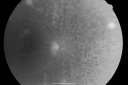

OD: Vertical C/D ratio is 0.1. There is extensive peripheral neovascularization. There is 2+ cystoid macular edema. There are patchy retinal hemorrhages and a moderately complete panretinal laser.

OS: Vertical C/D ratio is 0.1. There is 2+ cystoid macular edema. There is peripheral neovascularization and panretinal laser.

Photos confirm clinical findings.

FLUORESCEIN ANGIOGRAM: FA shows extensive active neovascularization in the mid periphery of each eye and leakage of fluorescein in the macula in the late frames of both eyes.

Proliferative Diabetic Retinopathy both eyes Type I Diabetic for 25 years837 views47-year-old woman with diabetes for 25 years and decreased vision for 3 months. OD 20/40, OS 20/40     (0 votes)